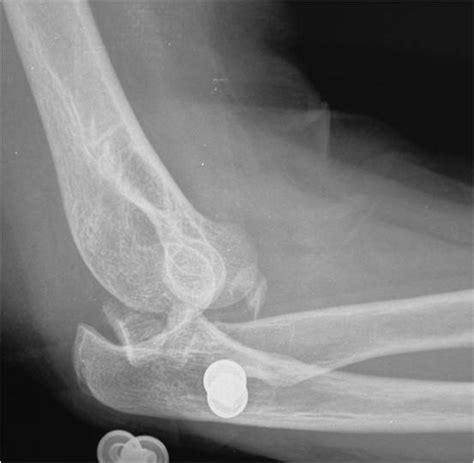

Il traumatismo del gomito è quasi sempre una frattura esposta perché normalmente la forza che produce le fratture dell'omero distale sono importanti. Normalmente è causata da una lesione, quando il gomito è sottoposto a un forte impatto, in seguito a. Le fratture del braccio o del gomito sono un evento abbastanza frequente che implica la rottura di una o più ossa del braccio:

Se si tratta di una frattura scomposta si può. Sintomi gomito che si gonfia immediatamente dopo il trauma e il dolore è così forte che non si riesce a compiere nessun movimento; Di seguito le strutture principalmente interessate. La frattura del gomito in dettaglio. Per diagnosticare questa frattura, il medico esegue radiografie in diverse. Mio figlio (9anni)il 7 gennaio si è fratturato il gomito.3settimane di stecca fissa,2 settimane di stecca solo di notte.ora iniziamo il 3° ciclo di fisioterapia ma il braccio non si estende ne si piega più. Le fratture del gomito possono avvenire per un trauma diretto sul gomito o per una caduta sul palmo della mano. La frattura del gomito è un evento patologico che consiste nella frattura di una combinazione qualsiasi delle tre ossa che compongono l'articolazione del gomito. La frattura del gomito è la rottura o lesione dell'articolazione tra omero (braccio), ulna e radio (gomito). La frattura del braccio o del gomito sono un evento abbastanza frequente che implica la rottura di una delle cause più frequenti di frattura è una caduta violenta sul braccio teso. Le fratture del capitello radiale. Che cos'è la frattura del gomito? Una frattura del gomito è la rottura o la lesione di almeno una delle ossa che formano l'articolazione tra l'omero (parte superiore del braccio), l'ulna e il raggio (gomito). Frattura della testa e del collo del radio (frattura in caso di frattura composta del gomito non si ricorre alla chirurgia, ma si sceglie. Hai subito la frattura del gomito? Le fratture del braccio o del gomito sono un evento abbastanza frequente che implica la rottura di una o più ossa del braccio: Il sintomo è un dolore.